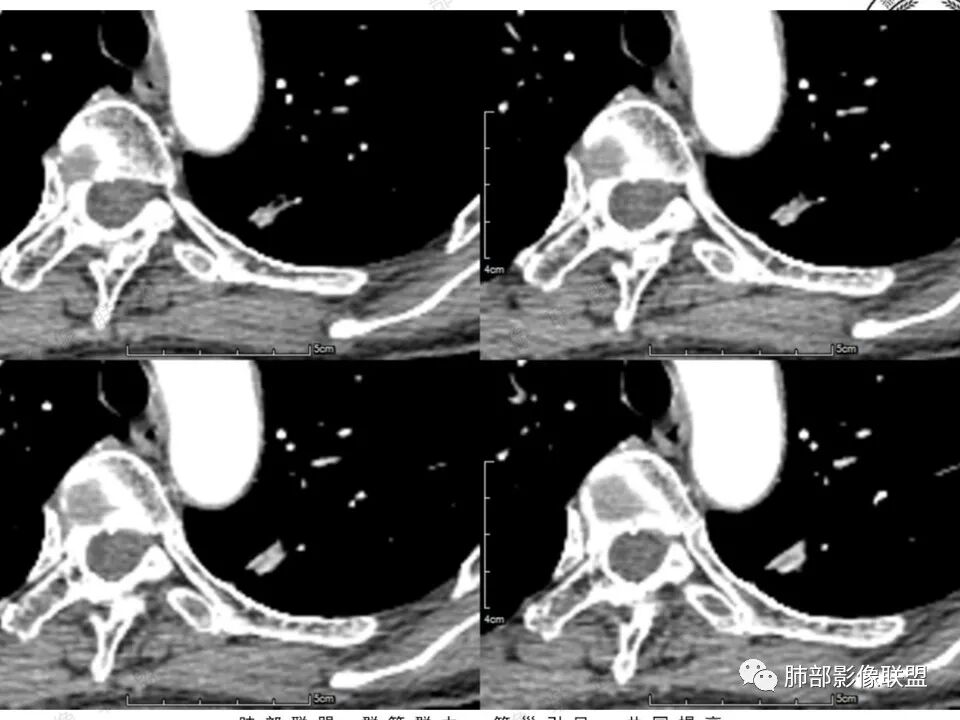

女,41岁,体检发现肺部结节。左肺上叶长形病灶,具有轻度膨胧感,刀切尖角征,胸膜粘连,早期强化见薄环强化征象,后期有延迟强化特点。病灶周围不是很干净。考虑结核肉芽肿或炎症肉芽肿。

左肺上叶尖后段实性结节,边缘有清晰磨玻璃,胸膜有牵拉凹陷,明显强化,CT值超过主动脉,考虑血管畸形(周围磨玻璃可能是出血),鉴别IAC(影像表现符合,强化不符)

患者中年女性,体检发现。胸部CT:左肺上叶后段长条形结节灶,边缘光滑,边界清楚,见分叶、毛刺、胸膜牵拉及平直征象。增强明显强化,内可见血管增粗,综合考虑恶性病变,浸润性腺癌可能大,鉴别结核。

41岁女性,左肺上叶不规则结节,边缘见似清非清的磨玻璃影,叶间裂牵拉。整体病灶边缘平直,强化明显。另左上叶外侧尚有一磨玻璃结节(蘑菇兄弟?),考虑炎性肉芽肿可能性大。强化太明显让人很纠结,会不会存在CD,但边缘又有磨玻璃影;腺癌、结核、隐球都没有见过强化这么明显的,强化程度与主动脉基本一致,不会是动静脉畸形吧。

1.中年女性,体检发现;2.左肺上叶后段长条形结节灶,边缘有膨隆,也有收缩,腺癌和炎性结节都可以,但是周围见边界清楚磨玻璃影强烈提示腺癌可能性。3.显著强化的肺结节,无论如何都应当引起我们的高度重视!尽管炎性病灶和新生物都可以,尽管强化程度不能作为诊断癌肿的依据。

4.本例结节强化程度明显低于主动脉,也缺乏血管畸形的典型的迂曲结构,血管畸形可能性不大。